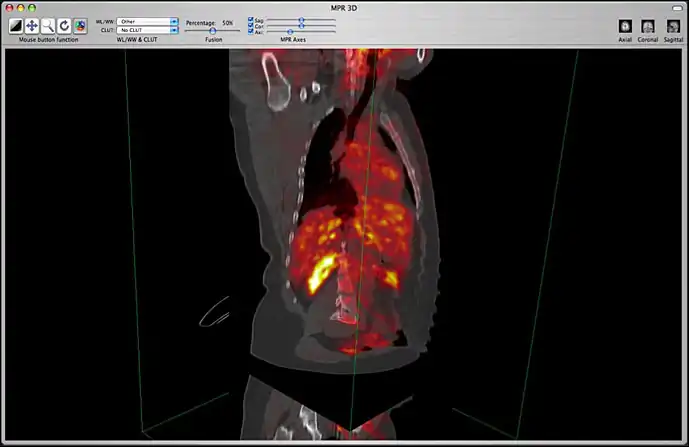

Image fusion is also available for 2D and 3D reconstructions implying that you can use image fusion along with MPR, Volume rendering, etc...

Image fusion in the 3D MPR window